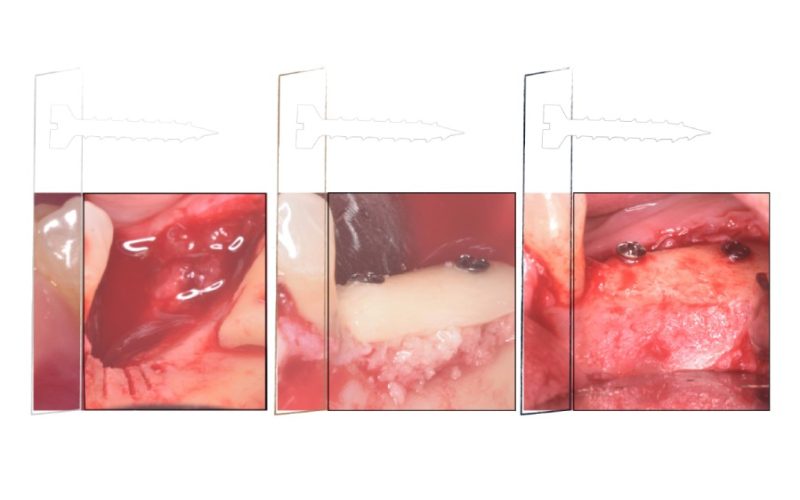

E-book PRF

Tenha em mãos um guia rápido e muito completo sobre a Fibrina Rica em Plaquetas, o PRF.

Descubra como o PRF pode melhorar os seus resultados em cirurgias orais e, consequentemente, melhorar os resultados de seu paciente.